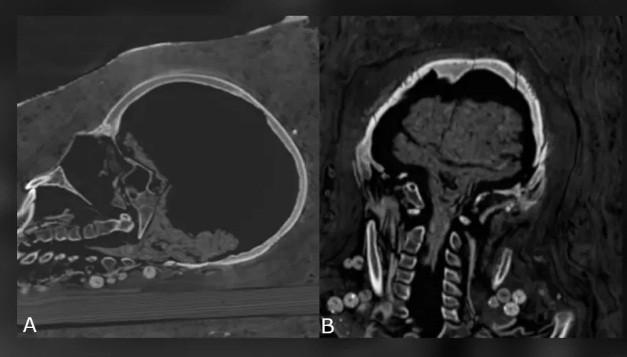

Hai người này qua đời khi còn khá trẻ. Trong khi người đàn ông cao 1,64m qua đời khi khoảng 25 - 30 tuổi thì người phụ nữ có chiều cao 1,56m chết khi 30 - 40 tuổi.

Tuy nhiên, hiện các chuyên gia chưa thể tìm ra nguyên nhân tử vong của họ. Các chuyên gia mới phát hiện người phụ nữ gặp một số vấn đế về sức khỏe, trong đó có bệnh viêm khớp.

Các chuyên gia dự định sẽ tiến hành những nghiên cứu sâu hơn để giải mã những bí ẩn còn lại về 2 xác ướp trên, bao gồm cả nguyên nhân tử vong.